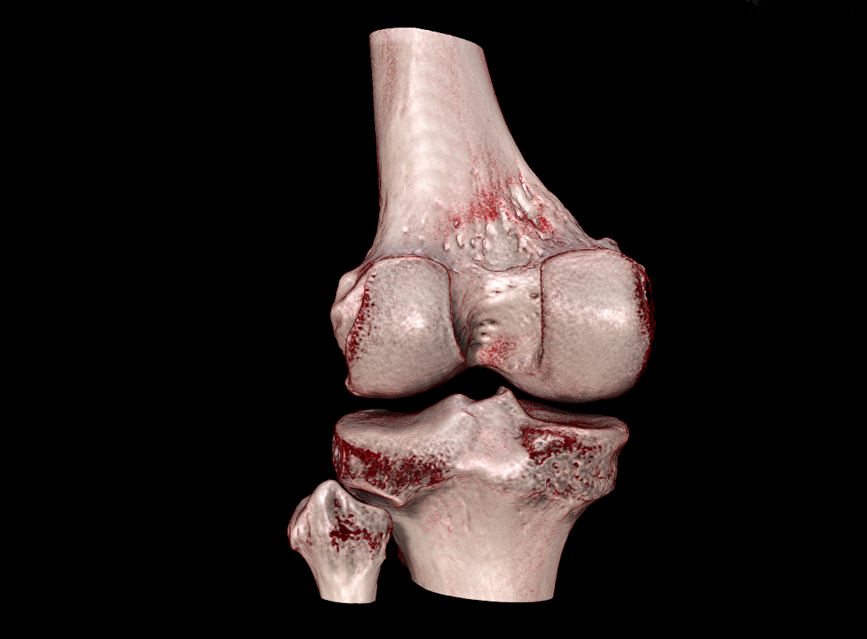

HRCT

High Resolution Computed Tomography. Outstanding image quality with a voxel size up to 100 µm